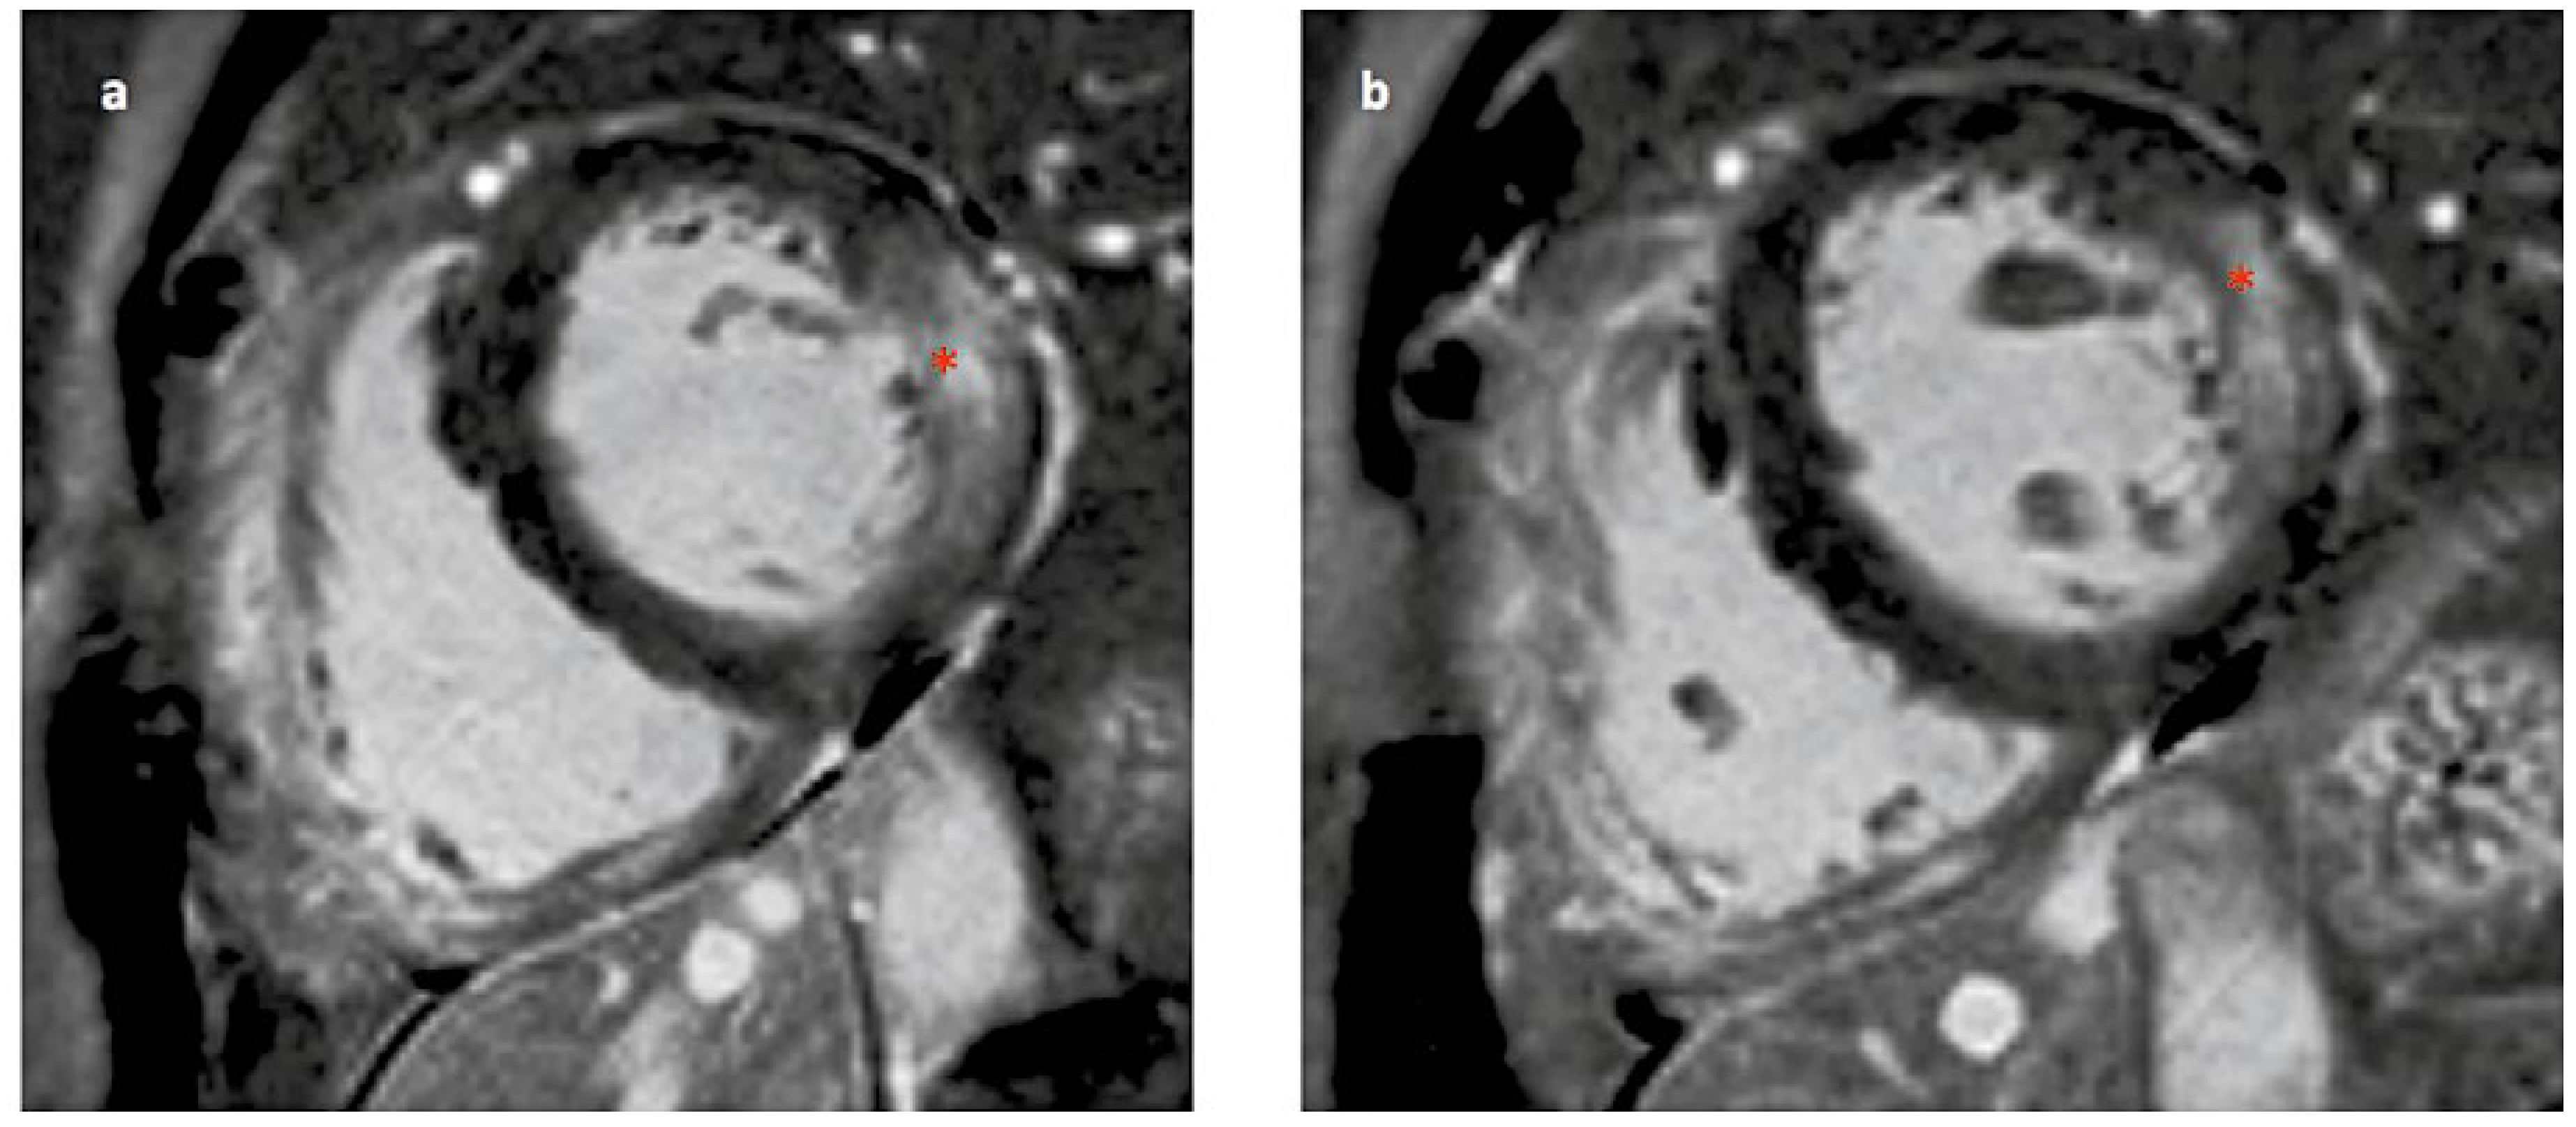

Wie manifestiert sich die Kardiomyopathie beim Morbus Fabry?

- Charakteristische EKG-Veränderungen und/oder echokardiografische veränderungen im Sinne einer linksventrikulären Hypertrophie können Manifestationen eines Morbus Fabry sein.